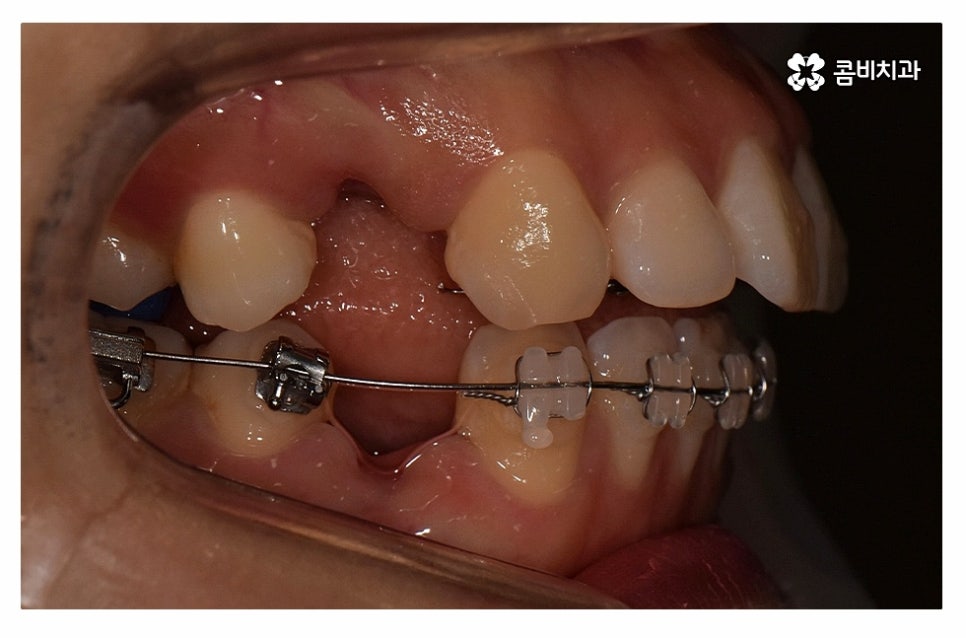

윗니는 설측교정으로 진행하고 아랫니는 일반적인 순측교정으로

치료를 진행하는 방식을 콤비교정이라고 부르고 있는데요.

콤비교정은 심미적인 치료 방법이며 혀가 위치한 아랫니는

순측교정을 하기 때문에 발음상의 불리함이나 이물감 등에서

유리하기 때문에 합리적인 치료 방법이라고 할 수 있어요.